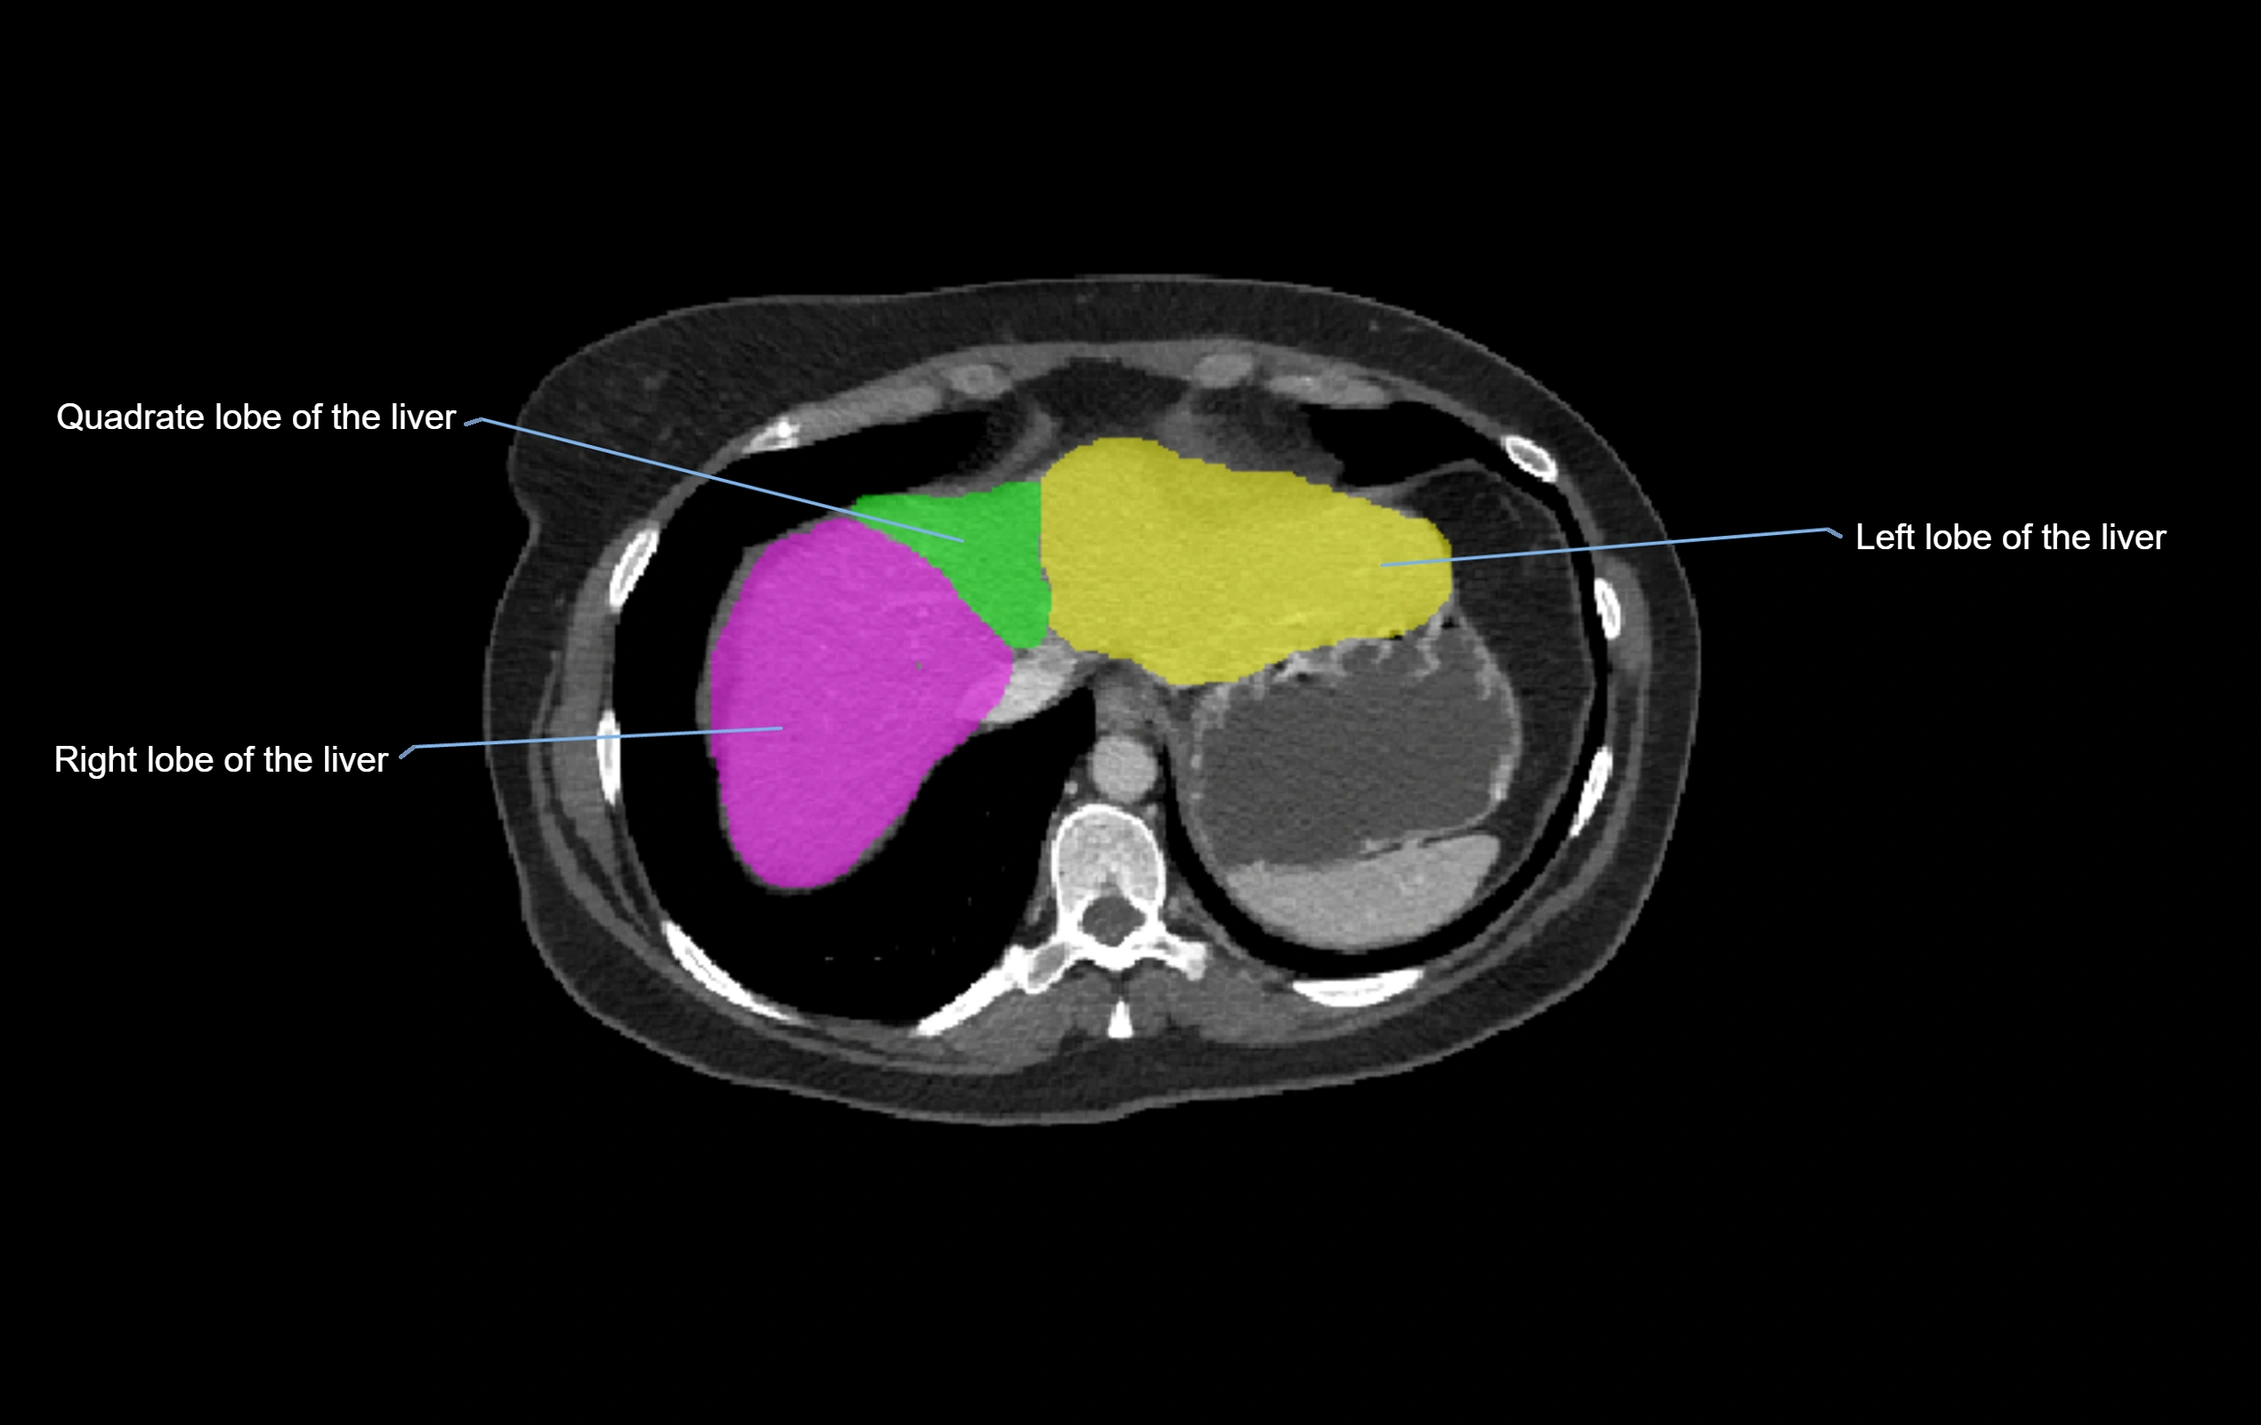

CT Image

image